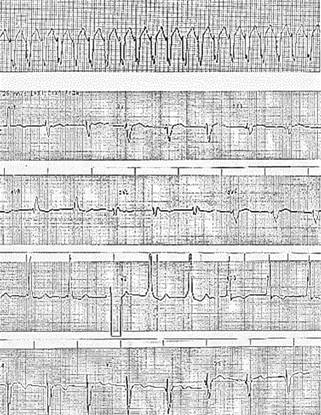

Paciente femenina de 21 años, de medio socioeconómico medio-bajo, con antecedentes de dificultad para subir de peso desde la infancia y cuadros de vías respiratorias muy frecuentes (al menos cinco a seis por año) caracterizadas por tos no productiva y fatiga, relata que durante sus años escolares no podía efectuar ejercicios ni deporte al igual que sus compañeros por disnea. Menarca a los 16 años, con ritmo irregular y núbil, al interrogatorio dirigido mencionó disnea de medianos esfuerzos de seis meses de evolución, consultó a facultativo quien diagnosticó estenosis mitral de origen reumático, le prescribió diurético mostrando mejoría. Acudió a urgencias por sufrir de inicio súbito: disnea a pequeños esfuerzos, diaforesis y sensación de palpitaciones. A la exploración: paciente angustiada, peso 39 kilogramos, talla 150 cm, IMC de 17.3 y en área torácica el ápex se encontró en el sexto espacio intercostal izquierdo sobre la línea axilar anterior. A la auscultación: soplo expulsivo aórtico grado IV/IV trasmitido a ambas carótidas; el primer ruido bajo en tono con soplo mesodiastólico grado III/IV. Abdomen normal, edema discreto en extremidades por debajo de rodilla con Godet +; no se detectaron pulsos arteriales en extremidades pélvicas estando presentes en las torácicas con 140 lpm. La tensión arterial en extremidad torácica superior derecha en 90/60 y los campos pulmonares con estertores crepitantes generalizados. Oximetría de pulso en mano derecha en 85% con aire ambiental que mejora a 94 con puntas de oxígeno a 3 L/min. Con impresión diagnóstica de coartación aórtica y lesión de válvula mitral se efectuó electrocardiograma, el cual reveló: taquicardia supraventricular de 240 lpm y vía accesoria oculta sugestiva de localización posteroseptal izquierda con conducción retrógrada (Figura 1A). Se administró amiodarona y cardioversión eléctrica, obteniendo ritmo sinusal con frecuencia cardiaca 66 lpm, AQRS en cuadrante superior derecho, QRS ensanchado por bloqueo de rama derecha, PR menor de 0.12 seg. y presencia de ondas delta (Figura 1B).

Figura 1: Electrocardiograma que muestra en A. Taquicardia supraventricular de 240 lpm y vía accesoria oculta sugestiva de localización posteroseptal izquierda con conducción retrógrada. En B. Posterior a amiodarona y cardioversión eléctrica obteniendo: ritmo sinusal con frecuencia cardiaca 66 lpm, AQRS en cuadrante superior derecho, bloqueo de rama derecha, PR menor de 0.12 seg. y presencia de ondas delta.